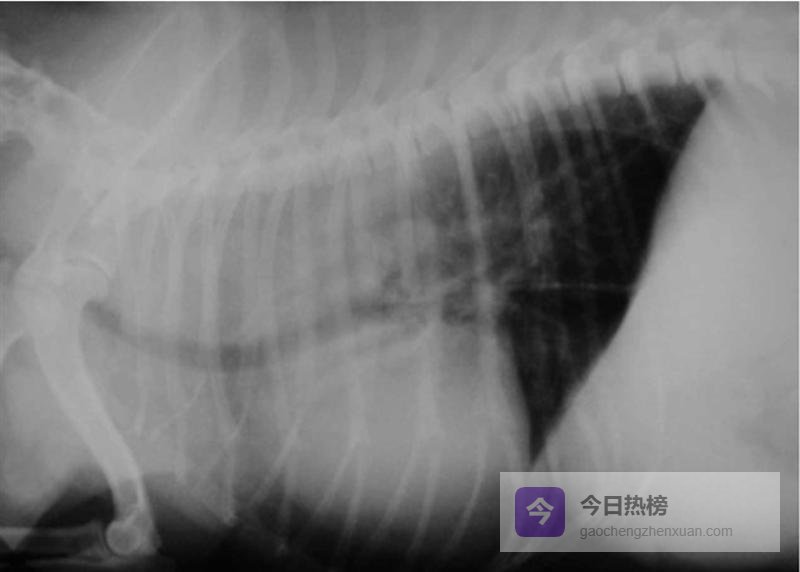

5.2 【 X光:先排除“其他元凶” 】胸片常规无异常,但别忽略巨食道症、血管环、异物、肿瘤或疝气(图2)。上消化道钡餐能动态观察胃食管反流、钡剂滞留、节段性扩张(图3),但正常猫狗也会偶见GER,因此必须结合临床症状与内镜病理综合判断。

图2. 巨食道症犬胸部影像